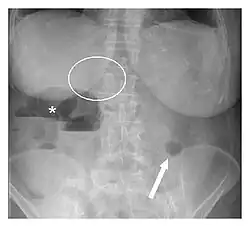

Plain abdominal radiograph showing Rigler's triad (pneumobilia indicated by the circle, ectopic gallstone indicated by the arrow, and bowel distension indicated by the asterisk).

Rigler's triad is a combination of findings on an abdominal radiograph of people with gallstone ileus, a condition where a large gallstone causes bowel obstruction. Rigler's triad consists of: (1) small bowel obstruction, (2) a gallstone outside the gallbladder, and (3) air in the bile ducts.[1] It bears the name of Leo George Rigler (1896–1979), who described it in 1941.[2][3] It is not the same as Rigler's sign.

It is most commonly seen in 6th to 7th decade of life and affects females more often. Most patients with gallstone ileus are asymptomatic. Due to the fistula formation between the small intestine and gallbladder, large stones can lodge in the small bowel, leading to its obstruction. Pneumobilia means air in the biliary tract. It is due to the transfer of air from bowel through the fistula into the biliary tract.